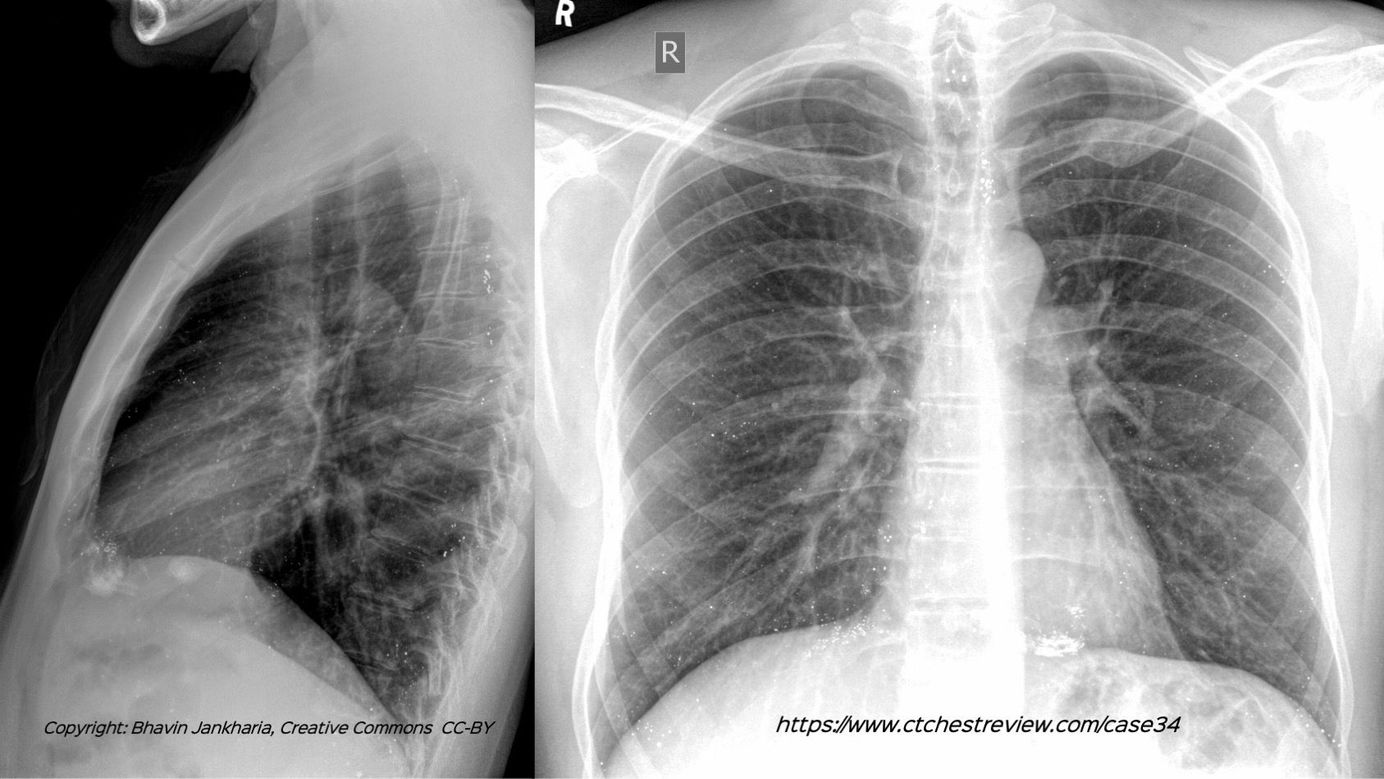

Case 29: The Slow Long Burn of Sarcoidosis Paid Members Public

The changing patterns of disease over 16 1/2 years in this patient with biopsy proven sarcoidosis